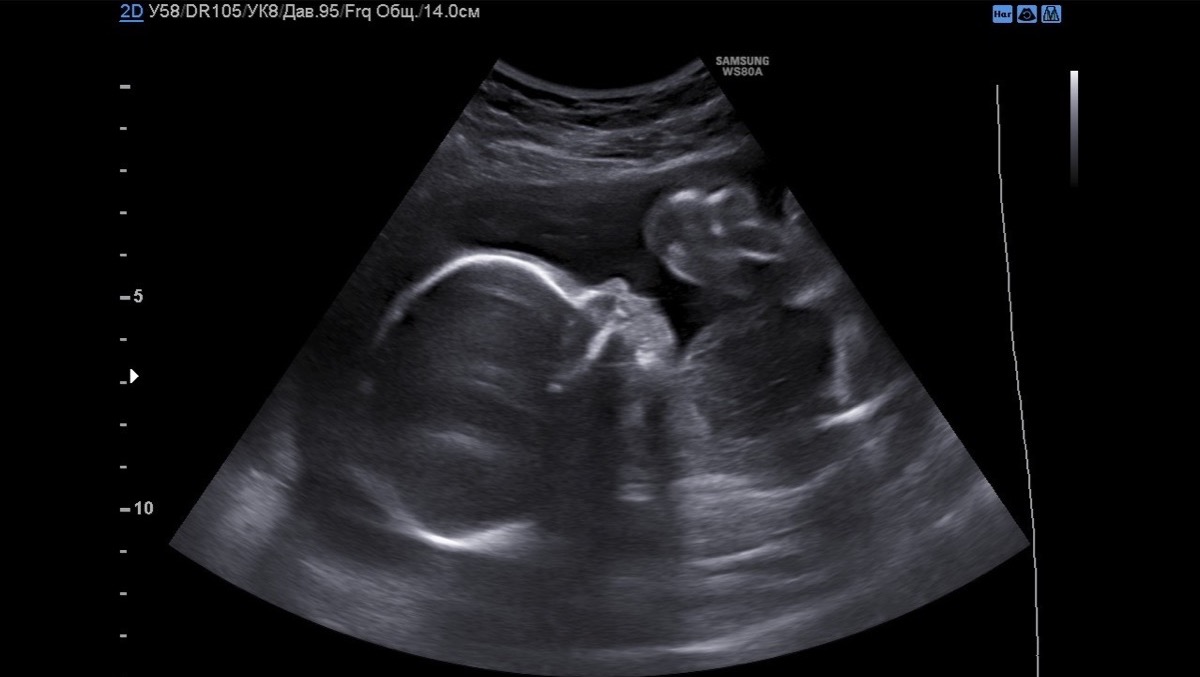

At the end of August of this year, when I woke up in the morning, I felt that something in my life had changed. But I couldn't understand what. After taking a pregnancy test, the results it was confirmed I'm pregnant. At first I was scared, but our inner feeling of happiness and joy overwhelmed us so much that we did not believe this was happening to us. I immediately began to take care of my child. I visited doctors regularly, took all the tests, ate right, walked by the sea and in parks, talked every day with the baby. I can’t express the emotions I felt when for the first time in my life I heard my child’s heart on an ULTRASOUND. The emotions i felt After the doctor proclaimed “Congratulations, you have a healthy girl.” Many years ago we came up with names for our children - Vasilisa; and already began to talk with her more and more, talked about what color her room would be and how we would all go to my grandmother's in the summer, how we would definitely get a dog ...

On the ultrasound, the specialist said that he couldn’t understand why he couldn’t see the right side of the diaphragm and saw some strange shadow in the place of the right lung. I didn’t understand what she was talking about at all, and after that I was sent to a specialist at the genetic center. The next morning we went to this center, during the ultrasound we cried and could not stop.

The doctor announced that our girl had a Right-sided diaphragmatic hernia. This is a very rare physical pathology, when a defect occurs in the diaphragm and the abdominal organs rise up through this defect and block the lungs, displacing the Heart. Only 15% of all registered cases will fall to the share of the right-sided one. In our country there is not a single specialist or technical ability to help such children, and that she will die within a few minutes after birth. Without an ECMO device, which is not available in Ukraine, only intrauterine surgery and surgery after birth can help her, but this is not done in our country.

After all, we were given a referral for Artificial Termination of Pregnancy. I could not take this step, because already at that moment I felt every day how my girl was moving and beating inside me. I knew that my child was healthy and had no chromosomal and genetic pathologies. After we decided to conduct all existing in-depth studies, our girl was checked by many specialists. They did an ultrasound, an MRI of the fetus, an ultrasound of the baby’s heart, they took an amniocentesis, all this in order to exclude any pathologies, a consultation was held. In conclusion, it was indicated that the child Congenital right-sided diaphragmatic hernia, all indicators of the lungs were calculated, that in other respects the girl is healthy and that she can be saved only with the help of intrauterine surgery. Through punctures in the abdomen at the 28th week of pregnancy, a balloon is inserted into the trachea, thanks to which the lungs grow and push out extra organs from the chest, which after birth will allow the baby’s lungs to work, and the defect in the diaphragm is sutured with its own tissues, after the child’s condition stabilizes, we contacted the Sant Joan de Deu hospital, namely Eduard Gratakos, who is a leading specialist in fetal surgery. He was one of the first to carry out such operations in the world, he said that he could and knew how to help us, that he had already performed similar operations and the children survived. He would try to do everything in his power. The cost of a fetal operation and assistance to a child after birth is 170,000 euros, this amount is unbearable for our family. We are forced to seek help, now I am 23.5 weeks pregnant. Thanks to everything that has happened to us lately, we know and believe that our girl can be helped, and we will never forgive ourselves for not trying to do it. I could not terminate the pregnancy according to indications in my country, knowing that my child is healthy, because every day I feel her inside, I feel how she actively moves when I eat something sweet, when I play the piano, when I sing, she especially likes it ... we love our girl very much . We are very scared, but we hope and believe that everything will work out for us. Our strong girl will also cope with all the trials that fell on her ...